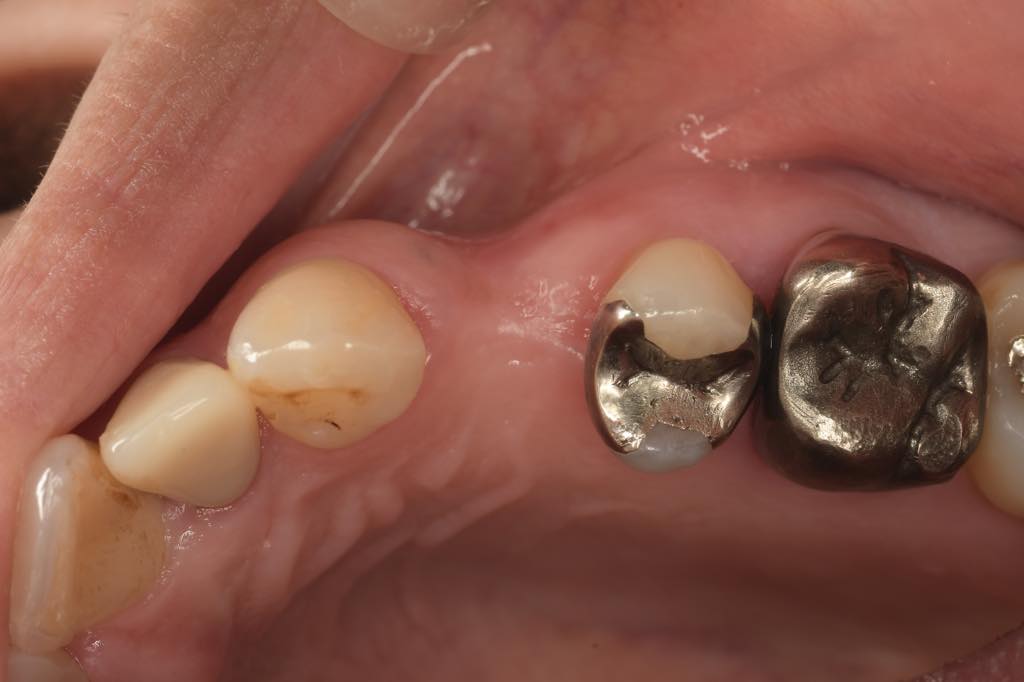

CASE 01

| 主訴 | 歯が割れた |

| 治療内容 | 左下6番 インプラント治療(骨の再生療法含む) |

| 治療回数 | 14回 |

| 治療費用 | ¥460,000 |

| 想定される副作用 | 腫れ、痛み |